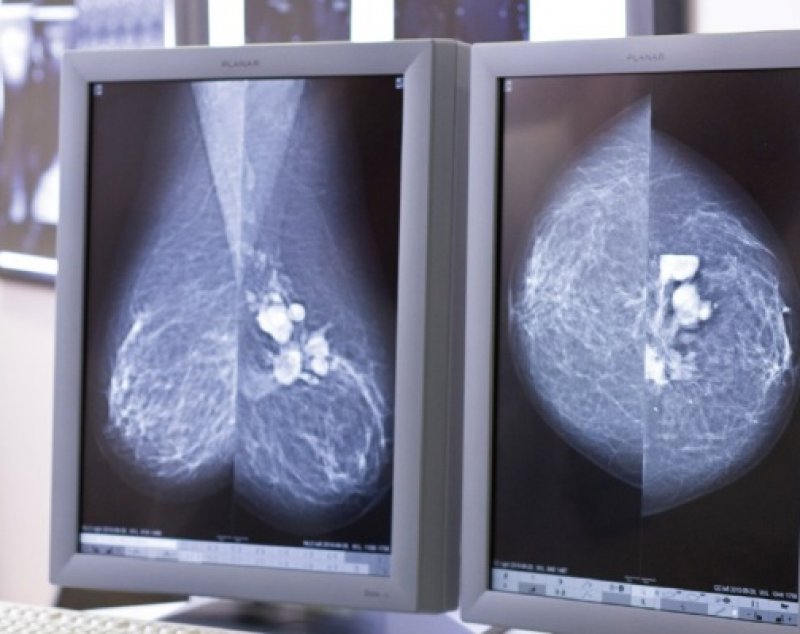

Digitalni uređaj za mamografiju, Mammomat Novation DR, pruža maksimalno pouzdanu dijagnostiku kojom možete brzo prekontrolirati građu tkiva dojke te otkriti mikrokalcifikate koji pokazuju moguće maligno oboljenje dojke, a koji su teško dostupni analizi na klasičnoj mamografiji.

Ovaj uređaj za mamografiju nove generacije jamči visoku pouzdanost uz minimalnu dozu zračenja.

Ponavljanje snimanja nije potrebno, jer postoji mogućnost kompjuterske obrade slike.